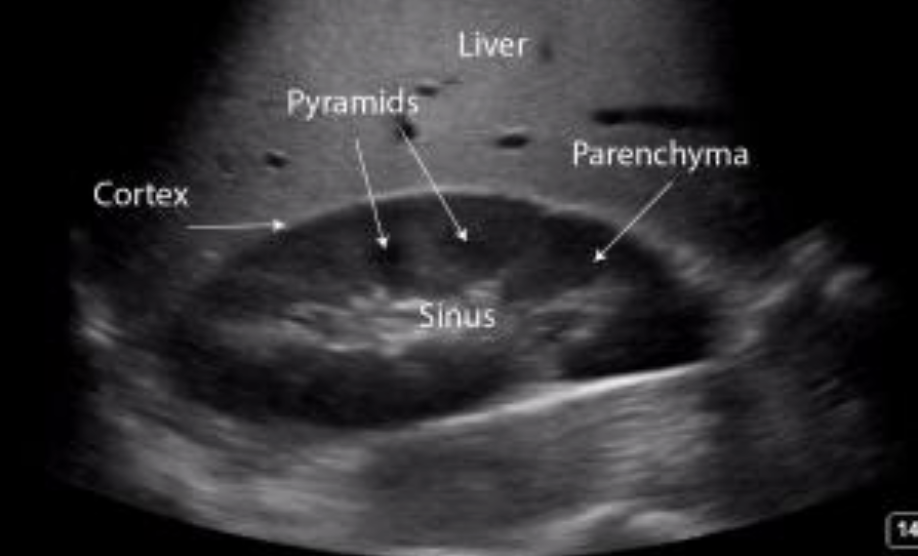

renal pyramids

renal artery

vascular supply

renal parenchyma